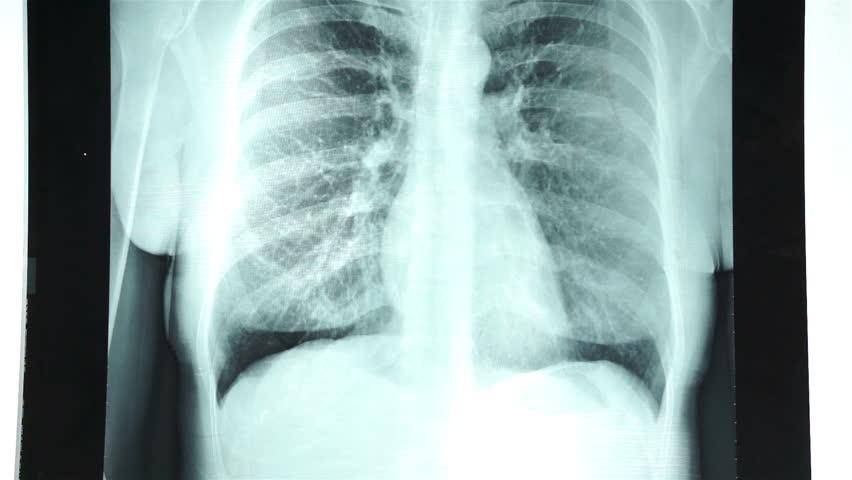

Rontgen dada atau rontgen thorax adalah foto dada yang menunjukkan jantung, paru-paru, saluran pernapasan, pembuluh darah, dan nodus limfa Anda. Rontgen dada juga bisa menunjukkan tulang belakang dan dada, termasuk tulang rusuk, tulang selangka, dan bagian atas tulang belakang Anda.

Rontgen thorax merupakan tes pencitraan yang paling umum digunakan untuk menemukan masalah dalam dada, terutama untuk mendiagnosis penyebab kondisi sesak napas.

Menurut Mayo Clinic, rontgen thorax dapat menunjukkan berbagai macam kondisi dalam tubuh Anda, termasuk:

- Masalah paru-paru, seperti kanker, infeksi, atau pengumpulan udara di ruang sekitar paru-paru (pneumothorax) dan kondisi kronis paru lain, seperti emfisema atau fibrosis kistik.

- Masalah jantung yang berhubungan dengan paru. Rontgen dada dapat menunjukkan perubahan atau masalah dalam paru-paru Anda yang masalahnya berasal dari jantung. Sebagai contoh, cairan dalam paru-paru (edema paru) merupakan hasil dari gagal jantung kongestif.

- Ukuran dan bentuk jantung Anda. Perubahan ukuran dan bentuk jantung bisa mengindikasikan gagal jantung, cairan di sekitar jantung (efusi perikardial), atau masalah katup jantung.

- Pembuluh darah. Letak pembuluh besar dekat dengan jantung Anda—aorta dan arteri pulmonal dan vena—terlihat pada sinar-X. Itu sebabnya, kondisi seperti aortik aneurisma, atau masalah pembuluh darah lainnya serta penyakit jantung bawaan dapat terlihat.

- Deposit kalsium. Rontgen dada bisa mendeteksi adanya kalsium dalam jantung atau pembuluh darah. Hal tersebut mengindikasikan adanya kerusakan dalam rongga jantung, arteri koroner, otot jantung, atau kantung pelindung yang mengelilingi jantung.

- Patah tulang rusuk atau tulang belakang.

- Perubahan pasca-operasi. Rontgen thorax bermanfaat untuk memantau proses penyembuhan setelah Anda melakukan operasi pada dada, seperti jantung, paru-paru atau esofagus.

- Alat pacu jantung, defibrilator, atau kateter. Rontgen dada biasanya diambil setelah penempatan suatu alat medis untuk memastikan semuanya berada pada posisi yang tepat.